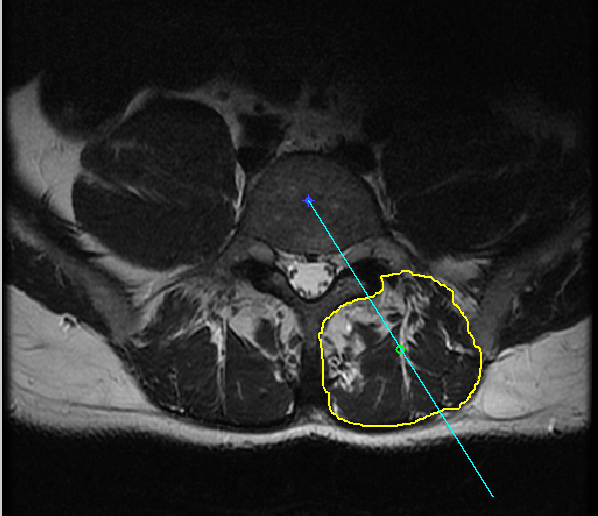

The first step is selecting the region of interest (ROI) from the MRI-defined lumbar muscles, which can be any among the erector spinae (ES) muscles, lumbar multifidus muscles (LMM) or psaos muscles, located either on the right or the left side of the spinal column [2, 5]. The user has to define the ROI by plotting a mask over the input image using livewire technique [21], as shown in Figure 2.

The livewire (or intelligent scissors) [21] is a semi-automatic image segmentation technique that allows the user to interactively select the ROI on an input image using mouse clicks along the contour of the ROI. When the user starts the selection of the ROI with a mouse click, a virtual wire is created linking the first clicked point (referred to as an anchor) to the point where the mouse is over, following a path that is as close as possible to image features detected as edges using Dijkstra’s lowest cost path algorithm. Figure 2 shows the result of a user segmentation using this tool.

2.5 Automatic detection of the center of the spinal column

The fat in the fragments of Erector Spinae (ES) muscles are quantified with reference to the center of spinal column. The center of spinal column can be selected by the user or it can be automatically detected. There are variations in the size and shape of the spinal column across different slices of MR Images of the same patient, which is the main challenge for automatic detection of the spinal column. We have adopted two different approaches for the automatic detection of the spinal column: a) with reference to spinal cord and b) using HOG features and an SVM classifier.

2.5.1 Detecting the spinal column with reference to the spinal cord

The spinal column is not consistent in size and shape across different MR Images. In contrast, the spinal cord is relatively consistent in size, shape and intensity level across different MR images.

The following steps are used to detect the center of spinal column with reference to the center of spinal cord:

Step 1: A central patch encompassing the spinal column and spinal cord is initially cropped from the input image. The central patch is used to avoid fat regions, while using intensity thresholds to detect the spinal cord, which is the brightest region in the cropped patch.

Step 2: Based on empirical investigation, an optimal threshold level (Otsu’s global threshold + 0.2) is used to detect the spinal cord over different MR Images. Using this threshold level the spinal cord is automatically detected in the process of grayscale to binary image conversion.

Step 3: After detecting the spinal cord region, the centroid of the spinal cord is calculated.

Step 4: The center of the spinal column is approximately fixed 55 pixels above the center of spinal cord. This value was selected based on experiment results and after testing across different images.

The evaluation of this method was carried out by manually cropping the spinal column and calculating the centroids. The centroids obtained by the manual method were compared to centroids calculated from automatically detected spinal columns. This method is quick and precise, but for a small number of images there are slight variations (upto 7 pixels in X-coordinate and upto 15 pixels in Y-Coordinate) in the automatically detected center of the spinal column when compared to the actual center of spinal column. However, these slight variations do not affect the reference for region-wise fat quantification.